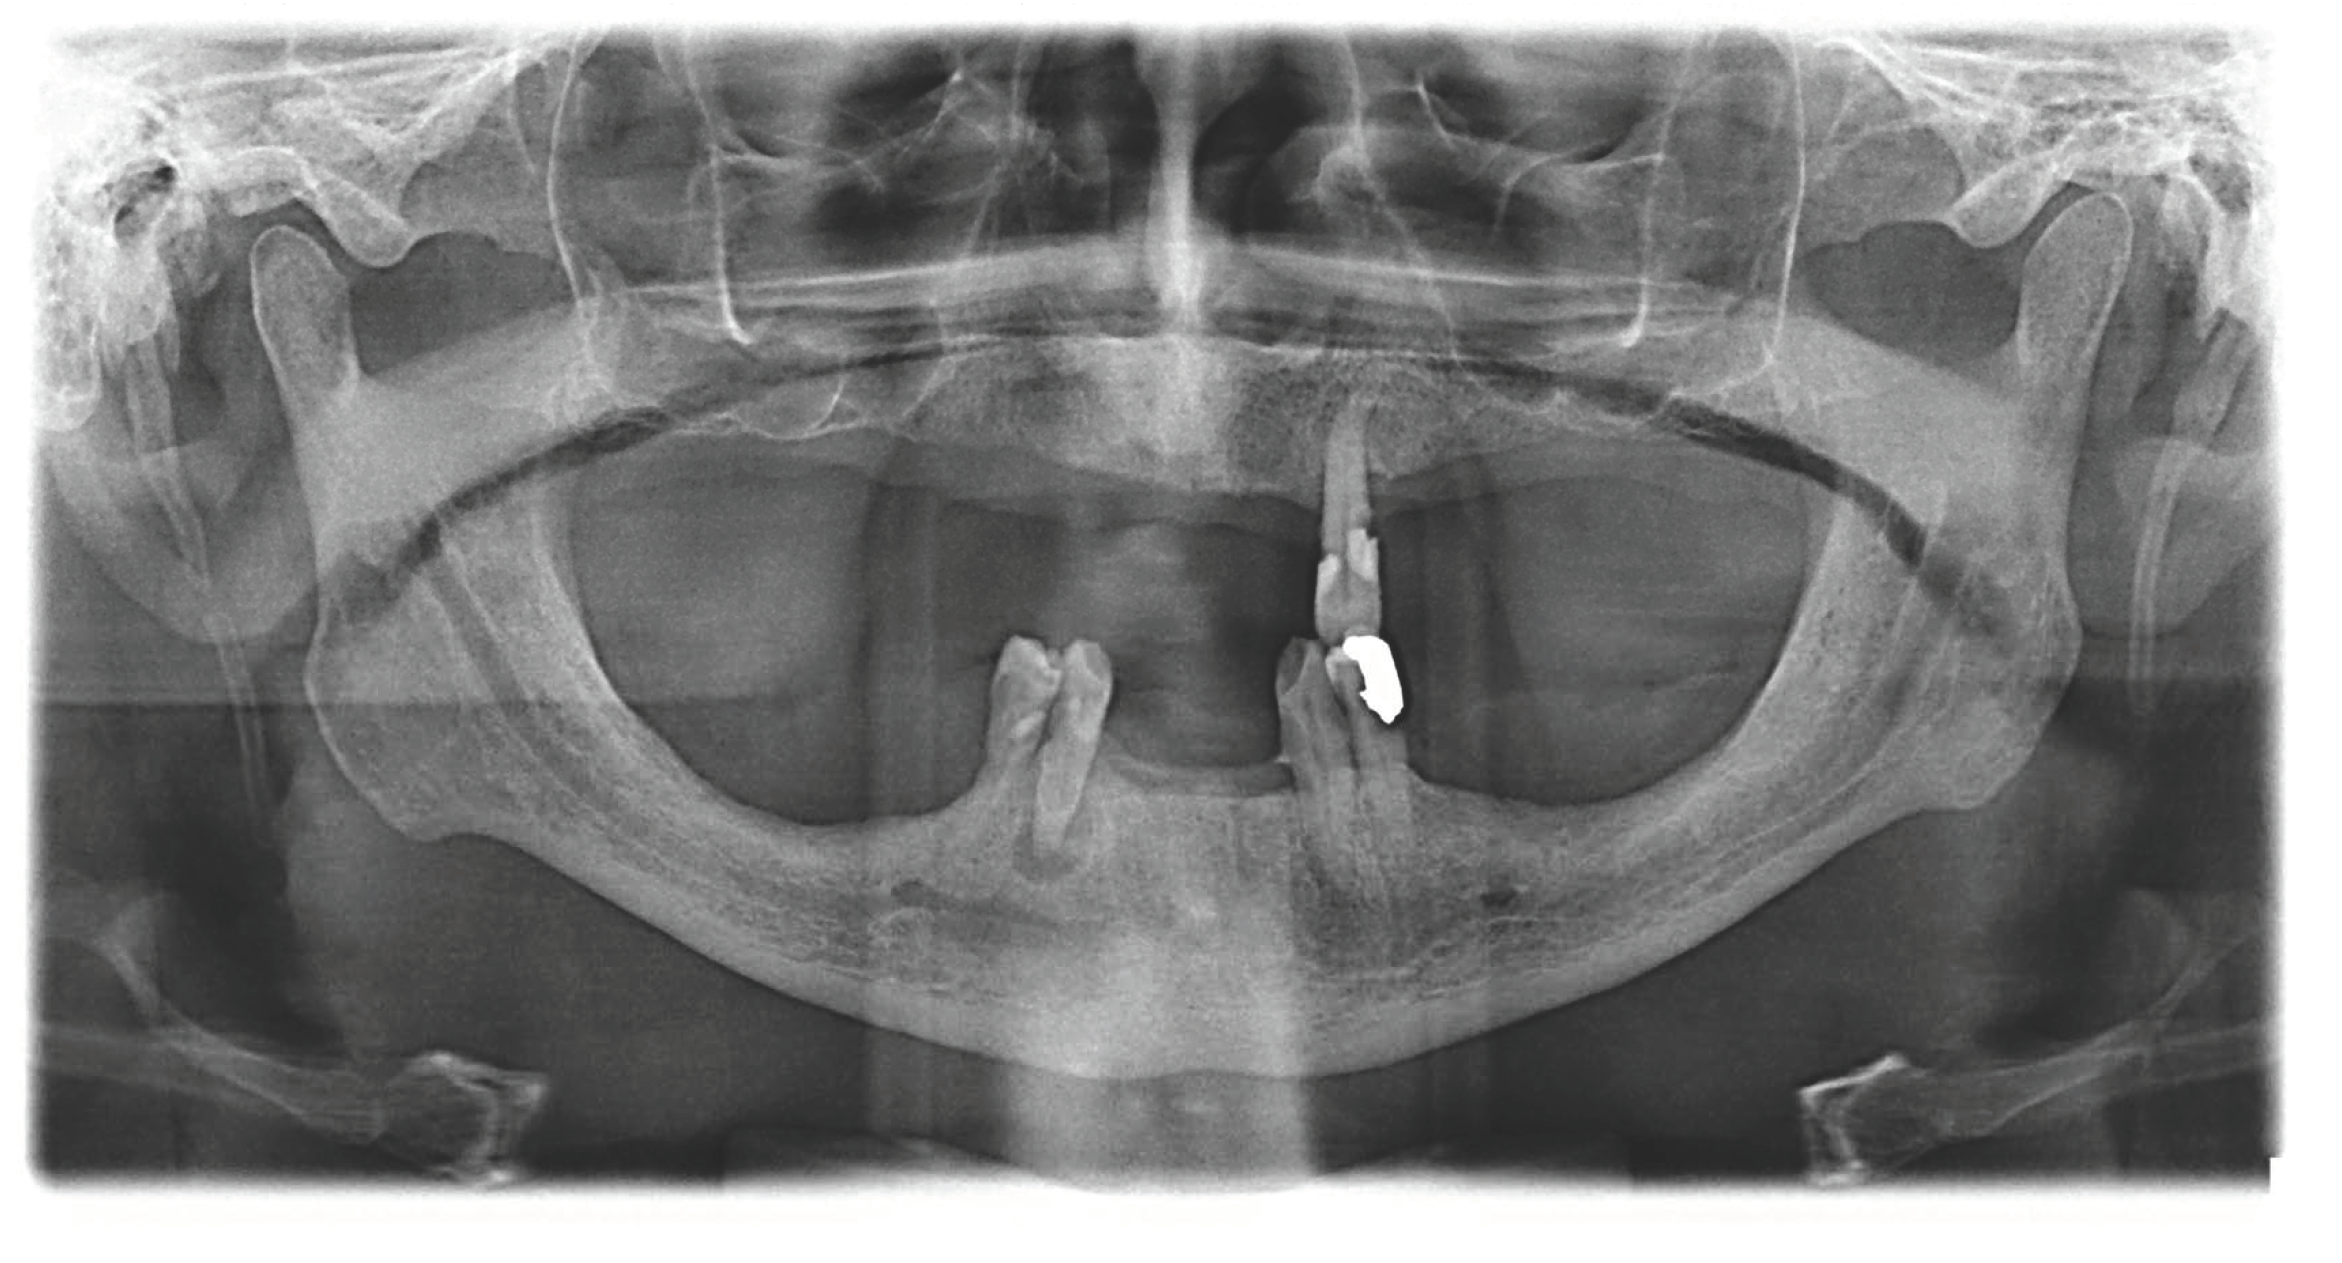

2. Materials and Methods

2.2. Surgical Procedures and Post-Operative Care